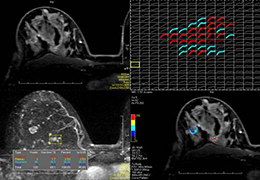

View X-Ray CT & MRI Scans Fast and Easily

Designed for surgeons, Pro Surgical 3D makes it easy to view patient scans quickly. Pro Surgical 3D facilitates the optimal 3D treatment and assessment workflows based on X-ray CT and MRI scans – and best of all, it’s FREE!

Designed mainly for CT and MR DICOM modalities.

Performs 3D reconstruction and volume rendering.

Multi-planar slicing.

Side-by-side comparative assessment for pre- and post-operative scans.